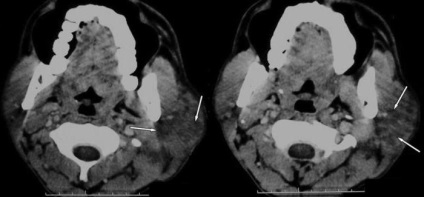

Ebben az esetben, ha az orvos gyanúja tályog, a betegnek meg kell alávetni CT vagy ultrahang.